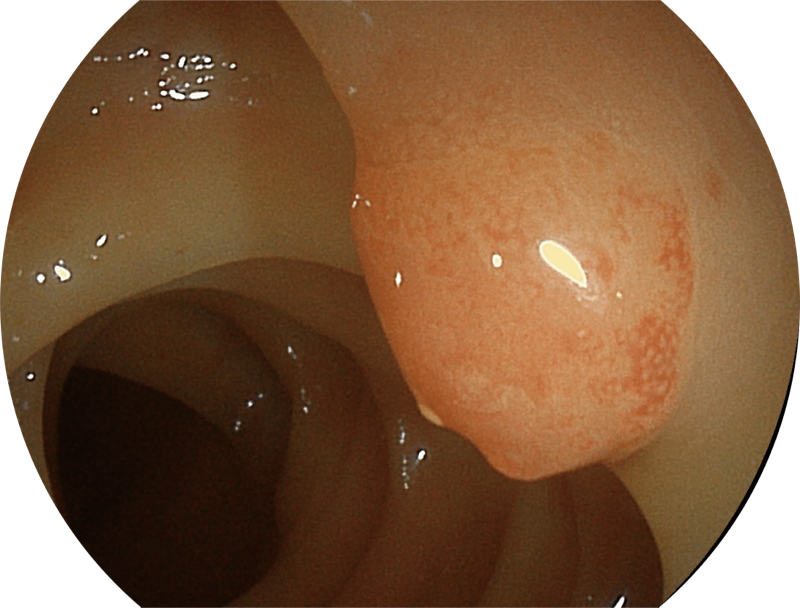

百万级像素高清传感器,1080P全高清视频信号输出,图像清晰。

能够凸显黏膜浅层和中层血管轮廓,适用于中、远景观察下的病灶识别和早癌筛查。

能够凸显黏膜浅层血管轮廓和黏膜表面微结构,适用于中、近景观察下的早癌精确诊断。